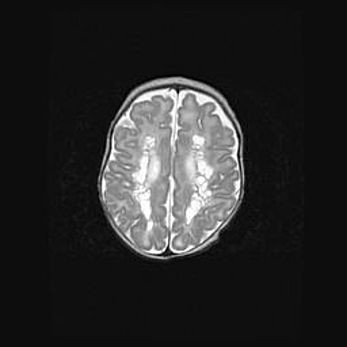

Церебральная ишемия II.

Возраст: 5 дней

Вес: 3400 г

Пол: женский

Окружность головы: 35 см

Срок гестации: 39 недель

Церебральная ишемия – это заболевание, характеризующееся недостаточностью (гипоксией) либо полным прекращением (аноксией) снабжения мозга кислородом по причине закупорки одного или нескольких сосудов. Это приводит к  что метаболическим расстройствам различной степени тяжести в тканях головного мозга, развитию коагуляционных некрозов и гибели нейронов.